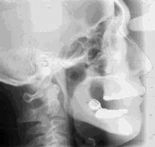

分析から咬み合わせを7mmあげました

唇に緊張感がでて顔が面長になりました。もともと面長だったそうですが、歯を失って長い間に咬み合わせが少しずつ低くなってしまったのです。古い入れ歯と比べて7mmも咬み合わせを上げました。

新しい入れ歯が入りました 下の親知らずが上の 奥歯と離れています

新しい入れ歯を 入れたときの変化 (赤い線)